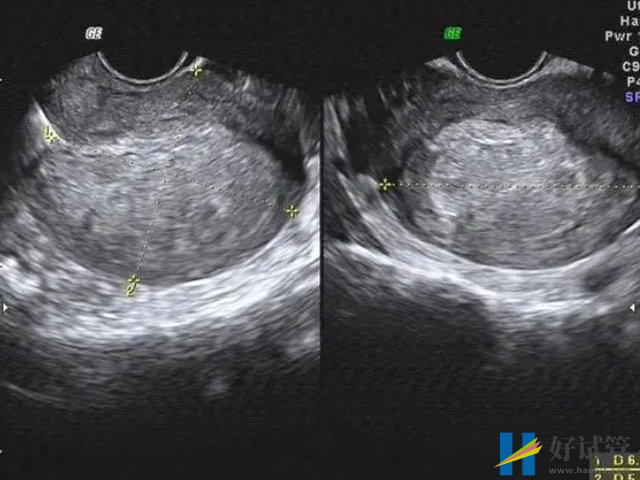

- 3. 超声检查:超声检查有助于诊断子宫息肉,但是虽然可以检测子宫内膜息肉的大小、数量和位置,但该检查不能提供明确的诊断;